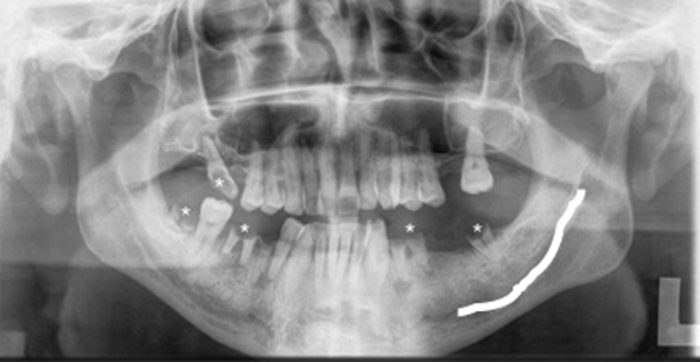

Dental disease, most commonly caries and impacted lower wisdom teeth, are frequent causes of referred otalgia. The imaging modality of choice in the assessment of teeth is radiography.

A commonly used radiograph is the orthopantotomogram (OPT). An OPT is a horseshoe shaped tomographic slice of both jaws, which can be useful in the assessment of caries, periodontal and periapical infections (Figure 5). It is a technique which is prone to positional errors and artefacts which can affect reliability of interpretation. Cone beam CT is being increasingly used in the dental profession but its use specifically for caries assessment is not recommended [2].

Figure 5: OPT of a different patient showing multiple carious teeth (*).

The left inferior alveolar nerve (white line) is easily identified.